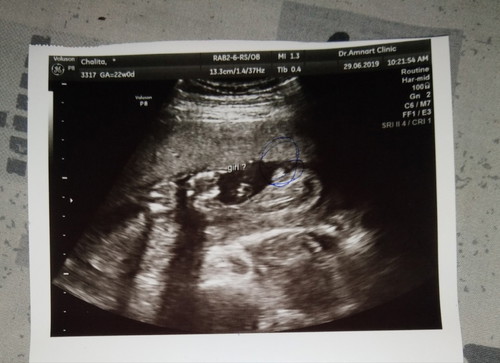

วันนี้ไปซาวด์มาคะ หมอบอกว่าลูกสาวแต่ยังไม่แน่ใจ100% ดูจากรูปแล้วเป็นลูกสาวหรือลูกชายคะ ?❤

น่าจะลูกสาวนะคะ ของเราเป็นผู้ชายมาเป็นจงอยน้อยๆแบบนี้ค่ะ 55555